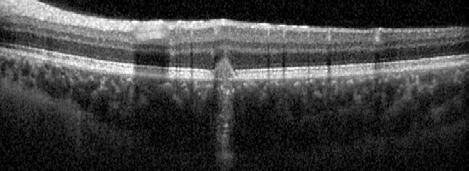

Type 3 MNV refers to the growth of vessels from the retinal circulation toward the outer retina. It is believed that vascular proliferation begins in the deep retinal capillary plexus, with the growth vector extending toward the outer retina. On FA and ICGA, Type 3 MNV appears as a hyperfluorescent intraretinal vascular complex with leakage in the late phases of the examination. Late-phase leakage ion ICGA is a unique feature of MNV lesions. Since these lesions originate from the retinal circulation, they never arise within the foveal avascular zone. Instead, they develop near its edge or at a variable distance from it, typically from the terminal portions of third-order arterioles and venules.5 (Figure 3)

Figure 3. Two examples of Type 3 macular neovascularization. In the first case, Indocyanine green angiography (B) and fluorescein angiography revealing the Type 3 macular neovascularization (arrowhead). Optical coherence tomography (C) showing the detachment of retinal pigment epithelium with the hyperreflective material related to the neovascularization. In the second case, optical coherence tomography (E) showing the intraretinal hyperreflective material related to the neovascularization with intraretinal fluid. Fundus autofluorescence (F) showing abnormalities of retinal pigment epithelium. Optical coherence tomography angiography (G) showing the neovascular lesion.